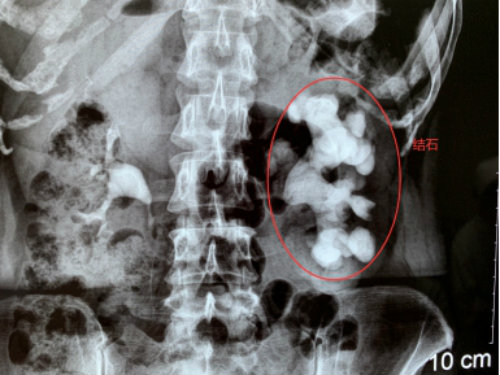

2019年11月18日,孝感一女子左腎里的結(jié)石長(zhǎng)成“精”,長(zhǎng)達(dá)12公分,形似一個(gè)“老生姜”,慕名到武漢京都結(jié)石醫(yī)院保腎取石,康復(fù)之際,被武漢多家媒體爭(zhēng)相報(bào)道后,一時(shí)間成了病房里的網(wǎng)紅。

18年前,魯女士在孝感當(dāng)?shù)蒯t(yī)院查出左腎小結(jié)石。因?yàn)閺膩?lái)沒(méi)癥狀,她就沒(méi)管過(guò)。最近兩年,她又因長(zhǎng)期右腰疼痛被查出腰椎間盤突出。上周,在準(zhǔn)備接受腰椎病治療的時(shí)候,CT結(jié)果提示她的左腎被結(jié)石撐滿,醫(yī)生建議她趕緊手術(shù),否則腎可能不保。

內(nèi)心十分害怕的魯女士專程趕到親戚推薦的武漢京都結(jié)石醫(yī)院,醫(yī)生指出,說(shuō)所患的是臨床上比較罕見(jiàn)的巨大鹿角形結(jié)石,處理起來(lái)很棘手。幸運(yùn)的是,她的雙鏡聯(lián)合微創(chuàng)保腎取石手術(shù)很成功,左腎里的“姜王”結(jié)石在一期手術(shù)中得到了有效處理,術(shù)后也恢復(fù)得不錯(cuò)。

為了有效預(yù)防結(jié)石再生,醫(yī)生對(duì)魯女士的結(jié)石做了成分檢測(cè),提示為感染性結(jié)石。醫(yī)生提醒,該類結(jié)石的生長(zhǎng)速度極快,手術(shù)取石后遵醫(yī)囑采取有效的藥物控制也是十分必要的。